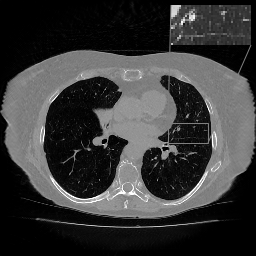

In Tables 1 and 2 we report these metrics on thorax CT data for straight and rotated patient orientation respectively, and the corresponding box plots are provided in Figures 1 and 2. Since the classical reconstruction methods such as FBP and TV are not trained on specific patient orientation, they are robust to rotations by design and are ommited in the second comparison. On the straight data, we observe that LIRE and LIRE+ noticeably outperform all the baselines. LIRE+ is able to achieve LIRE level of performance using only 99 iterations out of 1212. Full version of LIRE+ with 12 iterations gives a small performance improvement over LIRE. \partialU-net, while being fast, cannot match the reconstruction quality achieved by LIRE/LIRE+, even though it has more parameters. On the rotated data, we note that only LIRE+ is able to maintain the reconstruction quality thanks to the rotationally-equivariant primal cells, while all alternative models suffer from various amounts of performance degradation. It is wothwhile to note that the performance degradation is more pronounced in the learned post-processing baselines (Uformer and U-net), while learned iterative schemes seem to be more robust.

Examples of axial image slices of a ground truth image and the corresponding reconstructions with \partialU-net, LIRE and LIRE+ are presented in Fig. 3 with the respective difference maps in Fig. 4. Coronal view is provided in Fig. 5 and Fig. 6. For the image samples the HU range equals (-1000, 800) and (-1350, 150) for the ROI, while for the difference maps HU range equals (-1000, 800) and (-200, 200) for the ROI. From these examples we can see that LIRE+ gives sharper images with better HU calibration, while \partialU-net appears to slightly blur lung fissures. The difference maps suggest that particularly for LIRE+ image noise plays a large role in the image quality metrics.

Figure 3: (a) Axial slice of Thorax CT, HU range=(-1000, 800) and (-1350, 150) for ROI, (b) \partialU-net, (c) LIRE, and (d) LIRE+ 12 it.

Refer to caption

(a)

(b)

(c)

(d)

Figure 4: (a) Axial slice of Thorax CT, (b) \partialU-net error, HU range=(-1000, 800) and (-200, 200) for ROI, (c) LIRE error, and (d) LIRE+ 12 it. error